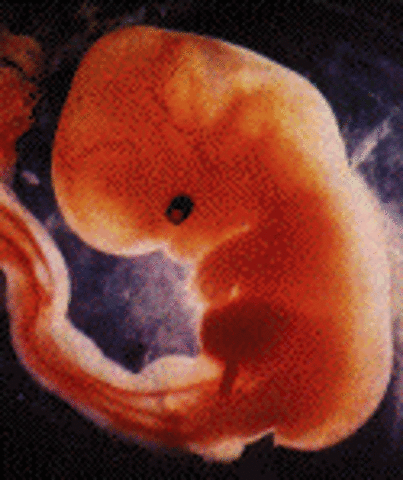

• Week 8: Movement

Week 8: Movement

At 18mm, the embryo is starting to try to move, the female would not be able to feel this movement until week 20. Muscle fibers and the pituitary gland are forming, the embryo also has its own blood type and clood cells.

Facts: -The stomach is being made from part of the gut

-The feet and hand buds have appeared